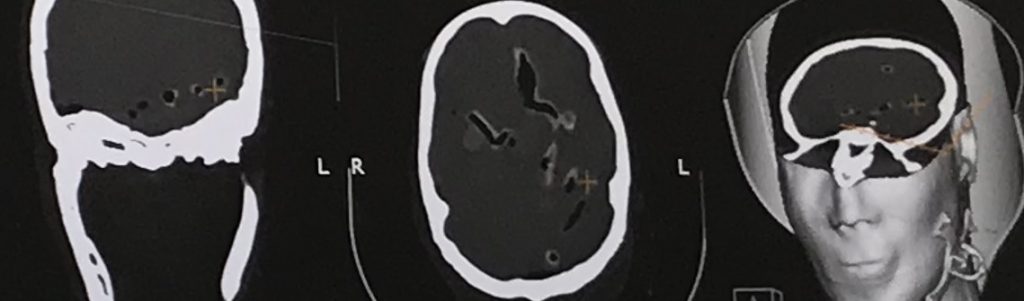

Reprenant la technologie développée pour pénétrer dans des milieux complexes et solides, les chercheurs ont construit des modèles de calcul pour simuler les perturbations que va subir le faisceau ultrasonore dans le crâne. « Nous avons d’abord fait une imagerie nanographique du crâne pour obtenir sa description géométrique, explique le chercheur. Ensuite, nous avons utilisé nos outils au CEA-List pour simuler la propagation du champ ultrasonore au travers de la paroi crânienne et pouvoir ensuite calculer les lois de phases nous permettant de corriger l’image ». Les chercheurs se sont servis de capteurs multi-éléments qui se pilotent indépendamment les uns par rapport aux autres, afin de focaliser en profondeur le faisceau ultrasonore. Ces capteurs sont notamment capables de retarder les émissions d’ondes pour compenser les perturbations provoquées par le milieu.

Grâce à ces techniques, les chercheurs sont ainsi parvenus à focaliser les ultrasons sur les tissus mous à l’intérieur du crâne et à améliorer nettement la qualité de l’image échographique. « La résolution de l’image est nettement meilleure, ajoute Sylvain Chatillon. Nous avons réussi à améliorer l’amplitude des échos d’environ une dizaine de décibels, ce qui est déjà beaucoup ». Pour le moment, ce résultat est une première preuve de concept. Les chercheurs ont démontré qu’à condition de connaître parfaitement la géométrie du crâne, et en considérant une hypothèse simplificatrice que le matériau constituant le crâne est homogène, ils sont capables d’améliorer notablement les caractéristiques de l’image obtenue en corrigeant les perturbations. « Toute la difficulté est de connaître la géométrie du crâne pour pouvoir appliquer ces algorithmes de correction des aberrations, poursuit le chercheur. »